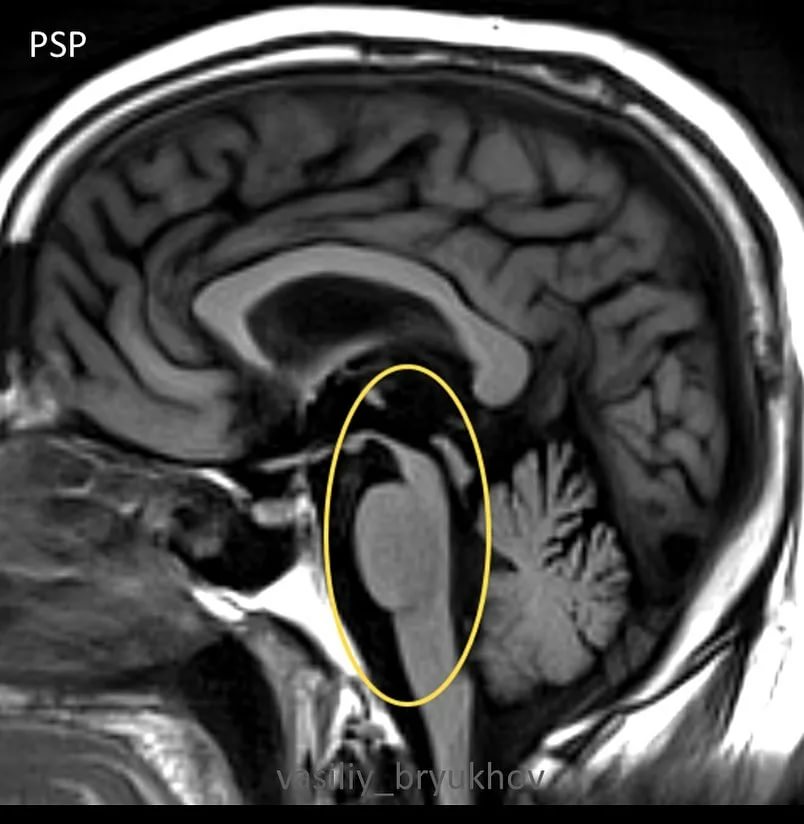

Прогрессирующий надъядерный паралич: полный гид по заболеванию для пациентов

Столкнулись с диагнозом прогрессирующий надъядерный паралич и ищете достоверную информацию? Эта статья подробно объясняет причины, симптомы, методы диагностики и лечения, чтобы вы могли лучше понять заболевание и управлять им.